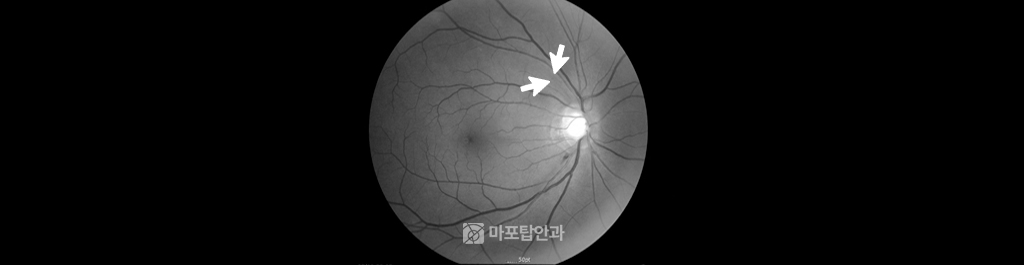

52세 여자환자의 안저 검진 사진입니다. 시신경하이측 시신경출혈이 관찰되었지만, 상이측에 이전 출혈로 인한 시신경섬유결손이 발생 및 녹내장으로 진단하여 치료중입니다.